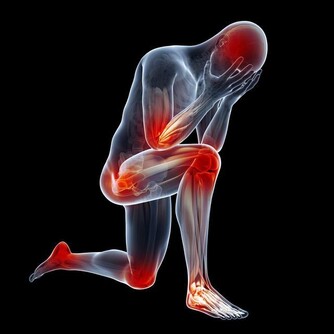

4、兩腿麻木無力、活動減少、腿腳冰涼、晚上疼醒:

要考慮下肢動脈硬化閉塞。

這點常常因為老人家覺得不重要不和子女說,會被忽視,拖到了腳壞死了才來就診,治療難度大,效果大打折扣。

5、兩手、兩腿突然冰涼、發白髮紫、腳趾頭髮黑:

要考慮急性動脈栓塞。

提醒大家要儘早就診,錯過了黃金搶救時間,到了截肢這一步就回天乏力了。